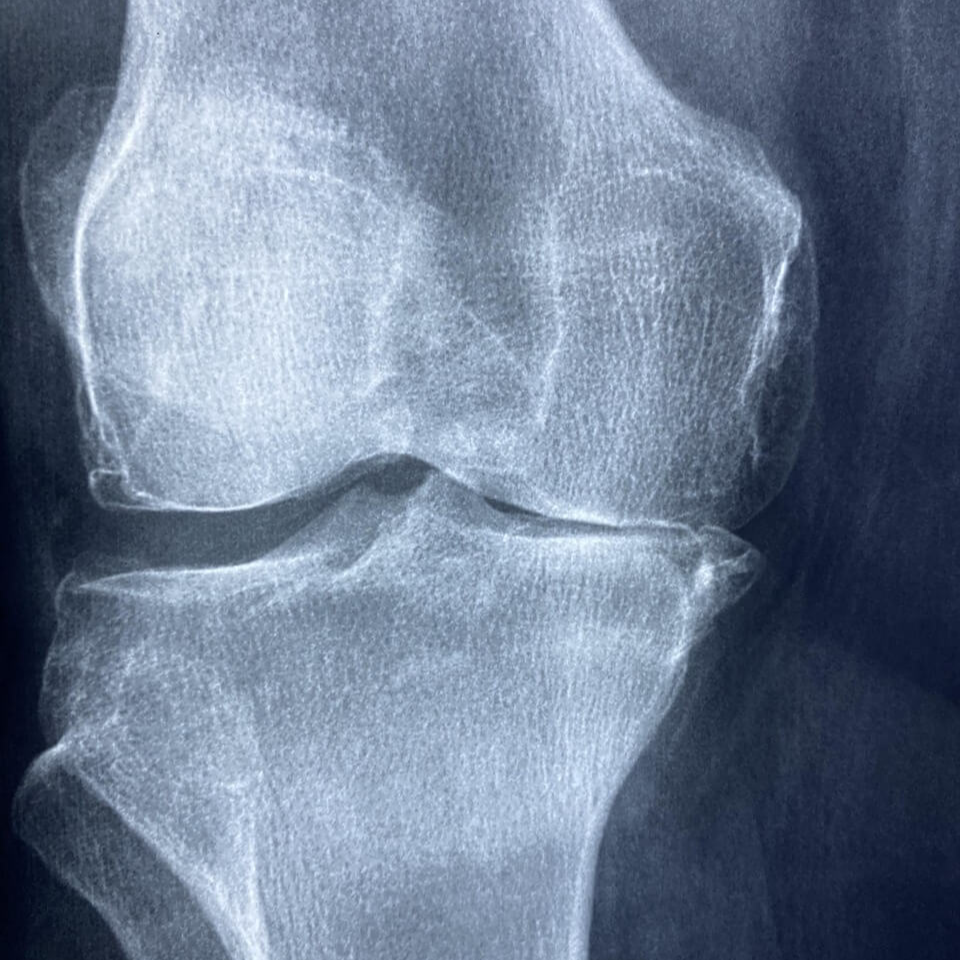

가장 기본적인 검사로, 뼈의 간격과 관절 공간 협착 여부를 확인할 수 있습니다. 관절염의 경우 관절 사이 공간이 좁아지고, 뼈의 가장자리에 골극(뼈 돌기)이 생긴 모습을 볼 수 있습니다. 하지만 연골은 X-ray에서 직접 보이지 않기 때문에, 연골 손상의 여부를 판단하기엔 제한적입니다.